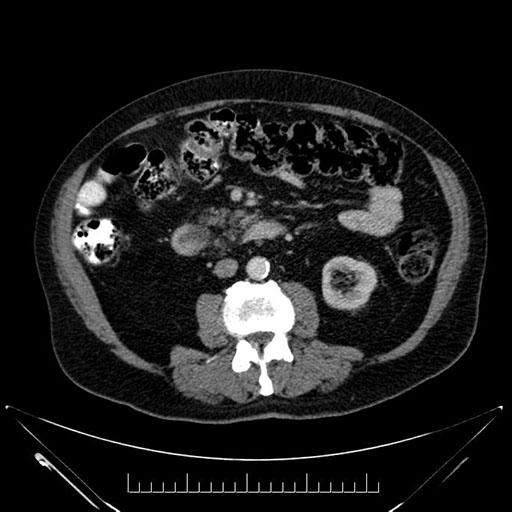

Whipple (pancreaticoduodenectomy) [case 7]

Imaging Analysis

Look through the patient's CT scan to identify any areas of concern for the necessary procedure.

Axial - stented